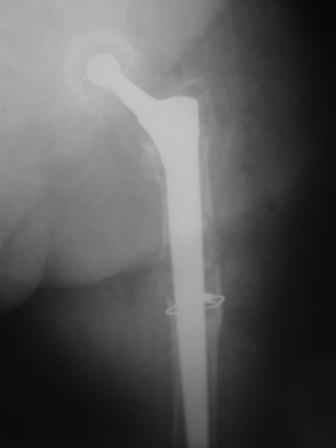

Спасибо за обсуждение. После нескольких дней тракции аппаратом сделали. Попытка закрытой репозиции не удалась из-за смещения по ширине, мешали фрагменты цемента. После их удаления репозиция получилась. Еще убрали немного цемента с ножки по латерльной стороне, чтобы обнажить 40-50 мм ее дистальной части, для плотной посадки гвоздя. Дальнейшее введение гвоздя было несложным. Протез показался нам стабильным в проксимальной части как латерально, так и медиально. Картинки в приложении.

THX for the discussion. After few days of traction by ex-fix the surgery was performed. An attempt of closed nailing was unsuccesful because of fragment translation, which was blocked by cement fragments. After removal of broken cement pieces reduction was reached "automagically". Also some cement from lateral part was removed by

chisel to expose distal 40-50 mm of the stem to allow tight fit of the nail. Further fixation by the nail was pretty easy and straightforward. Images attached. The stem looked stable in its proximal part both laterally and medially. Comments/critics are welcome.

* distal fixation of the nail is based near only on two screws : are they sufficient to secure a good stability before fracture consolidation?

I'd say yes because we use same 6 mm screws for femoral nailing and allow immediate weight-bearing regardless of fracture pattern.